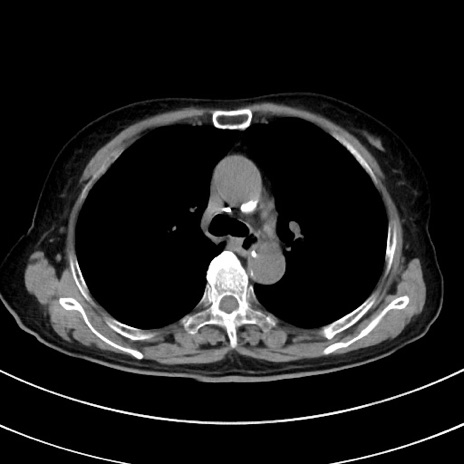

冠状断像